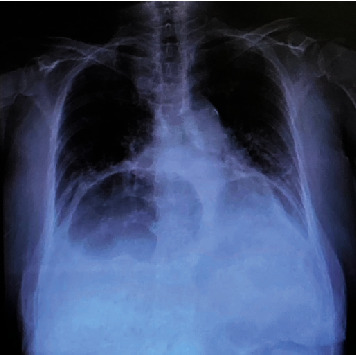

IV 型食管裂孔疝的特点是胃和相关器官(如脾脏、大肠、小肠和胰腺)通过食管裂孔疝出。这是一种相对罕见的食管裂孔疝,有时因胃嵌顿、胃内翻和绞窄而需要进行急诊手术。其中,小肠梗阻极为罕见,需要手术治疗。我们报告了一例因回肠嵌顿食管裂孔导致小肠梗阻而入院的 83 岁妇女的病例,该患者接受了紧急腹腔镜手术。

Type IV hiatal hernia of the esophagus is characterized by herniation of the stomach and associated organs, such as the spleen, large and small bowel, and pancreas, through the esophageal hiatus. It is a relatively rare form of hiatal hernia that sometimes requires emergency surgery due to gastric incarceration, volvulus, and strangulation. Of these, small bowel obstruction is extremely rare and requires surgery. We report the case of an 83-year-old woman who was admitted to the hospital for small bowel obstruction caused by an ileum that had incarcerated the esophageal hiatus; emergency laparoscopic surgery was performed.